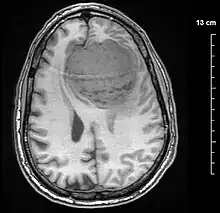

| A contrast-enhanced CT scan of the brain, demonstrating the appearance of a meningioma | |

Meningiomas are visualized readily with contrast CT, MRI with gadolinium,[22] and arteriography, all attributed to the fact that meningiomas are extra-axial and vascularized. CSF protein levels are usually found to be elevated when lumbar puncture is used to obtain spinal fluid. On T1-weighted contrast-enhanced MRI, they may show a typical dural tail sign absent in some rare forms of meningiomas.[17]